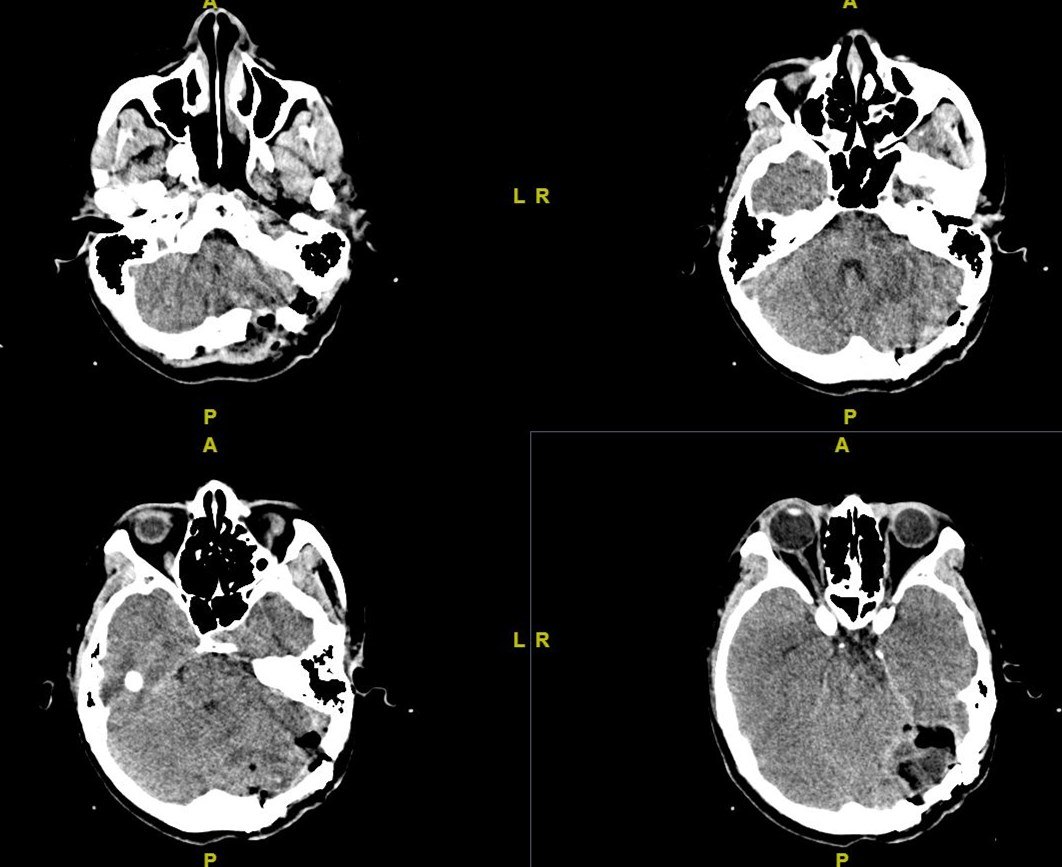

图2 ct平扫显示双侧横窦区域的异常高密度影(箭头所示),提示双侧横窦

头颅ct可见上矢状窦及右侧横窦高密度征

后床突 脑桥基底部 第四脑室 小脑蚓 小脑半球 颞肌 鞍上池 桥池 横窦